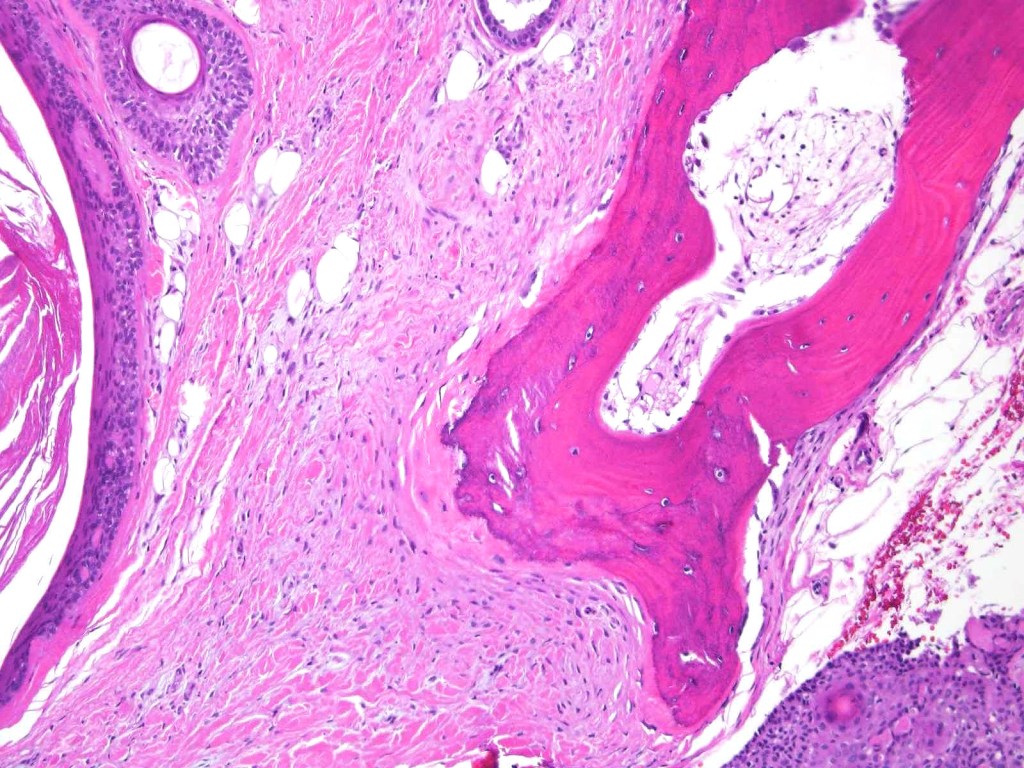

•Well circumscribed unencapsulated, nodular/multinodular silhouette composed of an admixture of epithelial & mesenchymal elements

•Ductal differentiation

•Stromal sclerosis & hyalinization

•Myxoid change

•Chondroid foci

•Calcification & osteoid

•So-called eccrine variant characterized by a pure population of small ducts compressed by dense collagen